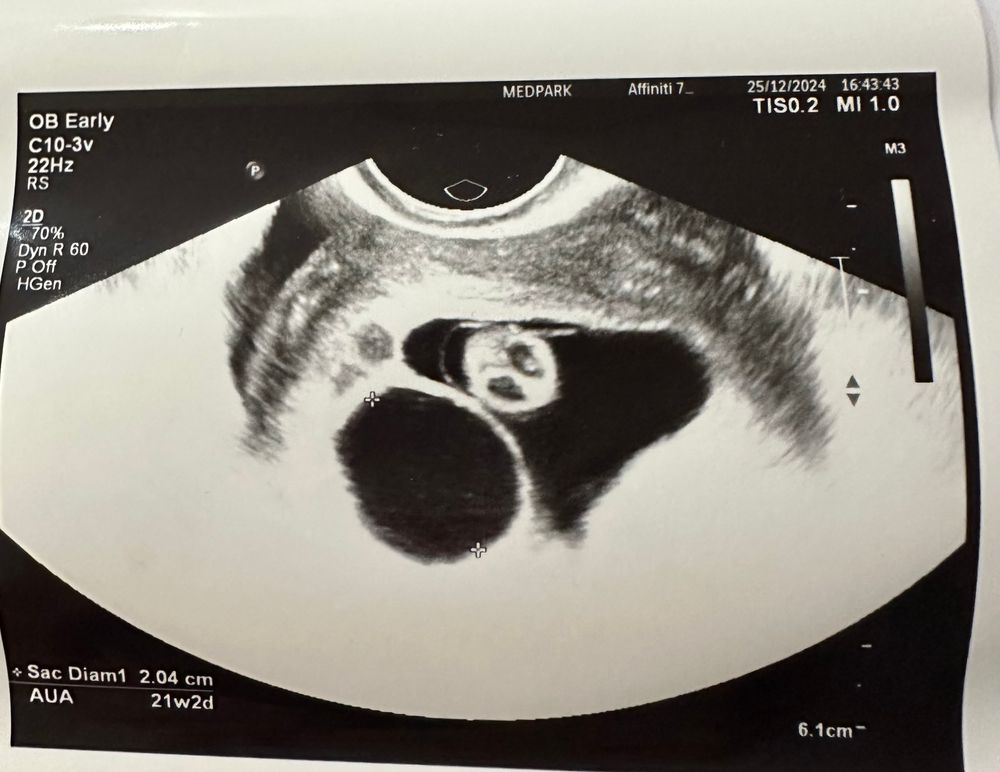

Результаты УЗИдевочки, я писала, что по снимку узи малышу будто бы мало места. Вот снимок:

Дарья, та узистка странная очень( ПЯ намеряла мало, по фото 1 две стороны. И как вы понимаете, это впритык к ктр. Это и по фото видно, что там малыш впритык. Но есть и другой ракурс, где места вроде побольше

На втором снимке, судя по всему, вид сверху, и на нем как раз видно, что малыш как бы в узкой части ПЯ находится - на первом снимке, видимо, как раз этот «срез» сфоткали, если бы узист чуть правее посмотрела, там уже ПЯ в два раза шире. На мой дилетантский взгляд, все должно быть хорошо. Плюс замеры вроде по 4 сторонам всегда делают 🤔 даже фолликулов, яичников итд.. Лучше переделать узи, да, чтобы было спокойно.

Череппааашка по имени Натааашка , мне просто рашмер ПЯ меряли по двум сторонам, что на первом фото. И как вы понимаете, оно почти как ктр вышло. Поэтому я сильно распереживалась(